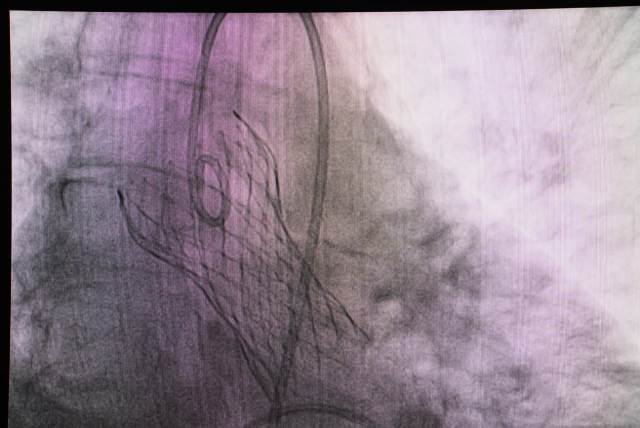

طب حلوان تنجح فى تغيير صمام الأورطى لمريضة تبلغ من العمر٧٢ فى  مستشفى بدر.. بالصور

أعلن الدكتور ممدوح مهدى، رئيس جامعة حلوان أن فريق  قسم القلب والأوعية الدموية فى "مستشفى بدر الجامعى" نجح فى تغيير صمام الأورطى بواسطة القسطرة القلبية "TAVI"؛ لمريضة تبلغ من العمر (72) عام، وتعتبر من الجراحات النادرة لصعوبة حالة المريضة لأن عمرها متقدم... مضيفاً أن العملية تعتبر من التدخلات الحديثة والصعبة بالقسطرة.

فى ذات الموضوع، قال الدكتور  ياسر صادق مدير وحدة قسطرة القلب أن العملية استغرقت ما يقرب من ساعة ونصف داخل غرفة قسطرة القلب بمستشفى بدر الجامعى، وتكمن صعوبتها فى أننا نتعامل مع أشياء دقيقة للغاية وتحتاج إلى تركيز عالى جداً من الفريق الطبى بـ"قسم القلب والأوعية الدموية"، حتى تخرج العملية بنجاح وبالشكل المطلوب، وحالة المريضة الأن مستقرة وتتحسن بشكل ملحوظ.